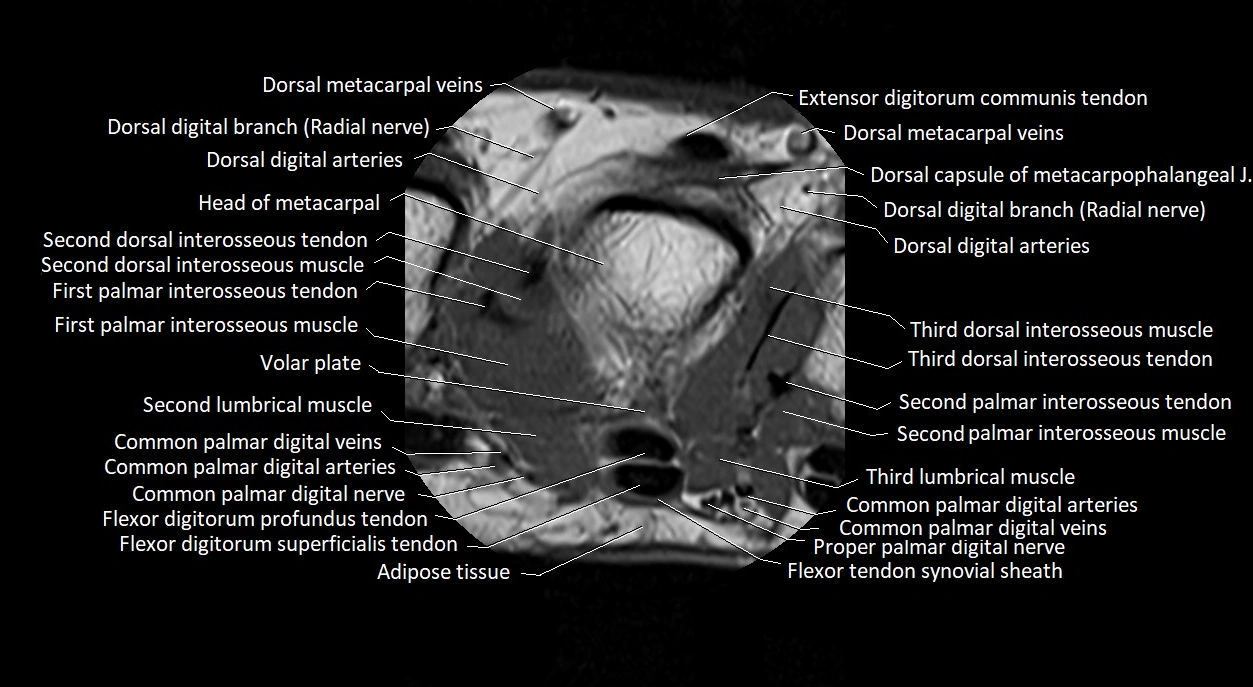

MRI images

image